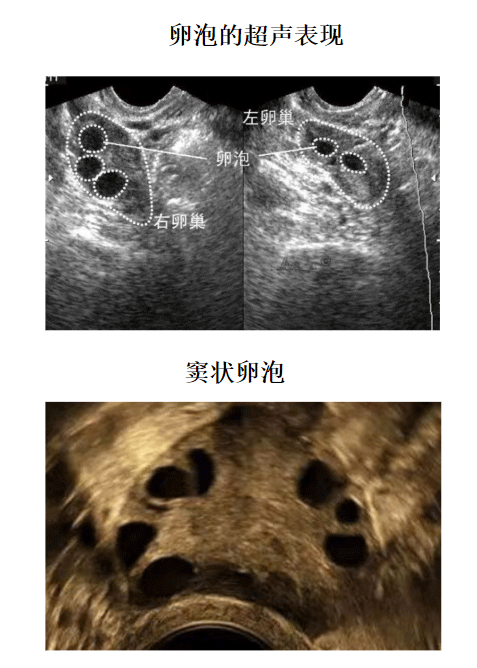

卵泡监测方法就是阴道B超检测,如果想要更加准确的判断卵泡发育程度、排卵日和黄体功能如何的话,建议配合基础体温检查,每次检查时间很短,不用担心花费太多时间。

2、多囊卵巢综合征引起的女性不孕,多囊卵巢综合征是引起女性排卵障碍的常见疾病,通过卵泡监测能够发现有很多细小的卵泡,但是不能发育成熟达到排卵要求。